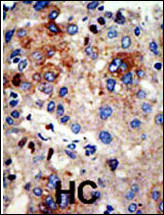

IHC 1/100-1/500 Human,Mouse,Rat